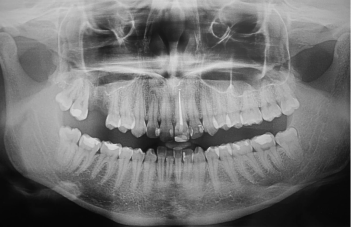

Implantologia dentystyczna to dyscyplina obecna na rynku usług medycznych w Polsce od końca lat osiemdziesiątych. Nasza klinika Dr Radosław Witkowski Opole oferuje usługi implantologiczne od 1993 roku. Implanty to nasza specjalność.

Obecnie implanty zębowe stanowią podstawę współczesnej rehabilitacji protetycznej w stomatologii i są dostępne dla każdego pacjenta bez ograniczeń wiekowych. Z perspektywy lat i osiągnięć medycyny XX wieku bezcenne są biologiczne, funkcjonalne i medyczne skutki ich zastosowania. W naszej placówce korzystamy z rozwiązań światowego lidera w dziedzinie implantologii stomatologicznej, co gwarantuje najwyższą jakość i bezpieczeństwo oferowanych implantów.

Implantologia dentystyczna to dyscyplina obecna na rynku usług medycznych w Polsce od końca lat osiemdziesiątych. Nasza klinika oferuje usługi implantologiczne od 1993 roku.